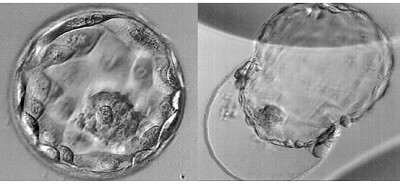

Thời điểm tối ưu để sử dụng progesterone trước khi FET vẫn chưa được xác định. Roelens và các đồng nghiệp tìm cách giải quyết vấn đề này và nghiên cứu các kết quả lâm sàng trong các chu kỳ FET của phôi nang được thực hiện vào ngày thứ sáu hoặc thứ bảy sau khi sử dụng progesterone. Các tác giả đã kiểm tra dữ liệu từ 619 phụ nữ đã trải qua FET phôi nang trước đó, giữa tháng 12 năm 2015 và tháng 12 năm 2017. Họ đã tìm thấy tỷ lệ sẩy thai và sinh sống tương đương giữa các nhóm. Điều thú vị là, khi họ thực hiện phân tích phân nhóm để so sánh kết quả sử dụng progesterone cho phôi nang ngày 5 và ngày 6, họ đã tìm thấy kết quả lâm sàng tốt hơn khi sử dụng progesterone lâu hơn ở phôi nang ngày 6. Tỷ lệ sẩy thai cao hơn đáng kể khi ET phôi nang ngày 6 được thực hiện vào ngày thứ sáu sử dụng progesterone (50%) so với ngày thứ bảy (21,4%). Cũng có xu hướng tỷ lệ sinh sống thấp hơn đối với phôi nang ngày 6 được chuyển vào ngày thứ sáu (21,5%) so với ngày thứ 7 của progesterone (35,5%). Những dữ liệu này cho thấy rằng sự phát triển của phôi về bản chất là khác nhau và đòi hỏi thời gian tiếp xúc progesterone lâu hơn để đồng bộ hóa tối ưu nội mạc tử cung.

Nhiều nghiên cứu đã cố gắng xác định xem phôi phát triển thành phôi nang vào ngày thứ sáu sau khi thụ tinh có khác biệt cơ bản với những phôi trở thành phôi nang vào ngày thứ năm sau khi thụ tinh hay không. Các nghiên cứu được thực hiện để xác định xem kết quả lâm sàng có khác nhau sau khi chuyển phôi nang ngày 5 và ngày 6 có kết quả mâu thuẫn hay không, đặc biệt là trong các chu kỳ FET, một phần, có thể là do sự khác biệt trong kỹ thuật bảo quản lạnh được sử dụng. Trong các nghiên cứu cũ, bảo quản lạnh phôi được thực hiện bằng kỹ thuật đông lạnh chậm, trong khi kỹ thuật thủy tinh hóa thành công hơn thường được sử dụng trong các nghiên cứu gần đây.

Năm 2019, Bourdon và các đồng nghiệp đã công bố một tổng quan hệ thống kiểm tra kết quả lâm sàng của chu kỳ tươi và đông lạnh sau khi chuyển phôi nang ngày 5 so với phôi ngày 6. Đánh giá của họ bao gồm dữ liệu từ 29 nghiên cứu, được công bố từ năm 2005 đến 2018 và phân biệt giữa các kết quả của kỹ thuật đông lạnh chậm và thủy tinh hóa. Phân tích tổng hợp này cho thấy tỷ lệ mang thai lâm sàng và tỷ lệ sinh sống cao hơn đáng kể sau ET của phôi nang ngày 5 so với phôi nang ngày 6 ở cả chu kỳ chuyển phôi tươi và chu kỳ FET với phôi đã được thủy tinh hóa trước đó. Tỷ lệ sẩy thai cao hơn đáng kể sau ET của phôi nang ngày 6 so với phôi nang ngày 5 trong cả chu kỳ tươi và chu kỳ FET sử dụng phôi đã trải qua quá trình thủy tinh hóa.

Câu hỏi chưa được trả lời là liệu kết quả vượt trội được thấy khi chuyển phôi nang ngày 5 có phải là do phôi chất lượng tốt hơn về bản chất với tiềm năng làm tổ vượt trội hay do đồng bộ hóa tốt hơn với nội mạc tử cung. Trong các chu kỳ tươi, tỷ lệ làm tổ giảm được thấy khi chuyển phôi ngày 6 đã được quy cho sự đồng bộ dưới mức tối ưu giữa phôi và nội mạc tử cung thay vì khiếm khuyết vốn có trong phôi ngày 6. Kết quả kích thích buồng trứng có kiểm soát trong sự phát triển nội mạc tử cung với WOI trước đó, sẽ không tối ưu cho phôi nang ngày 6 phát triển chậm. Phù hợp với phát hiện này, các nghiên cứu cũ cho thấy phôi nang ngày 6 có tỷ lệ làm tổ cao hơn và tỷ lệ mang thai diễn tiến khi được đồng bộ hóa trong chu kỳ FET so với ET tươi.

Trong phân tích tổng hợp này, kết quả lâm sàng tốt hơn cũng được thấy trong các chu kỳ FET sau khi chuyển phôi nang ngày 5 so với phôi nang ngày 6, điều này sẽ chống lại sự đồng bộ nội mạc tử cung dưới mức tối ưu là nguyên nhân duy nhất dẫn đến kết quả lâm sàng kém hơn sau khi chuyển phôi ngày 6. Thực tế là kết quả vượt trội đã được ghi nhận trong phôi nang ngày 5 sẽ phù hợp với giả thuyết rằng phôi phát triển chậm có tiềm năng làm tổ thấp hơn, có lẽ do sự khác biệt về trao đổi chất hoặc thượng di truyền. Tuy nhiên, những phát hiện của Roelens và các đồng nghiệp sẽ cho thấy rằng phôi nang ngày 6 phát triển chậm hơn có khả năng cấy ghép nhưng có thể có WOI khác và có thể hẹp hơn so với phôi ngày 5. Với phôi nang ngày 5 được rã đông sau khi trữ lạnh bằng phương pháp thủy tinh hóa, kết quả lâm sàng tương tự đã được thấy khi ET diễn ra vào ngày thứ sáu hoặc thứ bảy của progesterone, nhưng kết quả phôi nang ngày 6 đã thấy tốt hơn với thời gian sử dụng progesterone lâu hơn.